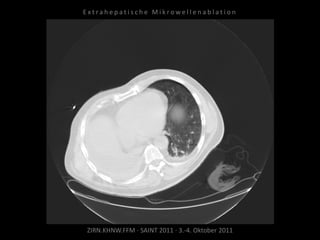

Ausgangsbildgebung:

CT vom 27.10.2010

Situation:

Nur eine Lunge und in dieser eine

(kleine) Metastase.